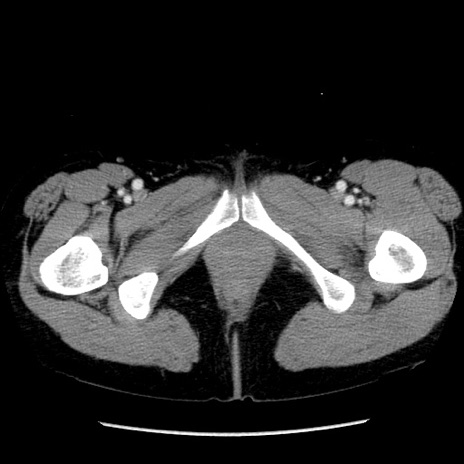

症例6(横断像)

【症例】50歳代女性

【主訴】下腹部痛

【既往歴】卵巣癌術後(8年前に当院で卵巣摘出)

【身体所見】 意識清明、腹部:平坦、腸蠕動音→、やや硬、下腹部自発痛・圧痛あり、反跳痛あり、筋性防御なし。

【データ】WBC 16000、CRP 0.01